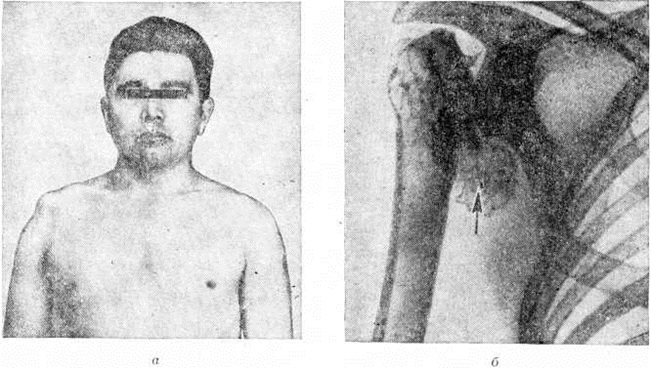

Атрофические парезы более выражены в дистальных отделах рук и проявляются внешне развитием так называемый когтистой или обезьяньей кисти. Характерно парциальное распределение мышечной атрофии, что объясняет частое несоответствие между выраженностью истончения мышц и степенью двигательных нарушений. При распространении процесса на боковые канатики спинного мозга возникают симптомы поражения проводящих путей с появлением проводниковых нарушений чувствительности и развитием спастических парезов ног. Из черепномозговых (черепных нервов в процесс часто вовлекаются V, VII, IX, X, XII пары. Вегетативно-трофические нарушения представлены широко и полиморфно: существенно выражена дезорганизация периферического кровообращения, гипергидроз (смотри полный свод знаний), может наблюдаться синдром Бернара — Горнера (смотри полный свод знаний: Бернара — Горнера синдром). В коже и её придатках обнаруживаются атрофические и дистрофические изменения, отмечаются гиперкератоз и нарушения пигментации (рисунок 2). Ногти утрачивают нормальный блеск, становятся матовыми, ломкими, рубчатыми. Отмечаются панариции, которые протекают без болей. Могут наблюдаться трофические изменения костей, суставов. Особенно характерны кифосколиоз грудного отдела позвоночника (смотри полный свод знаний: Сколиоз), деформации грудной клетки в виде реберного горба (рисунок 3). Отмечаются выраженные деструктивные изменения костей, иногда сопровождающиеся патологический переломами при небольшой травме; нейродистрофические остеоартропатии, протекающие без болевого синдрома; выявляются грубые деструктивные изменения костной ткани, сочетающиеся с её гипертрофией.

Рис. 2. | ||

Рис. 3. | ||